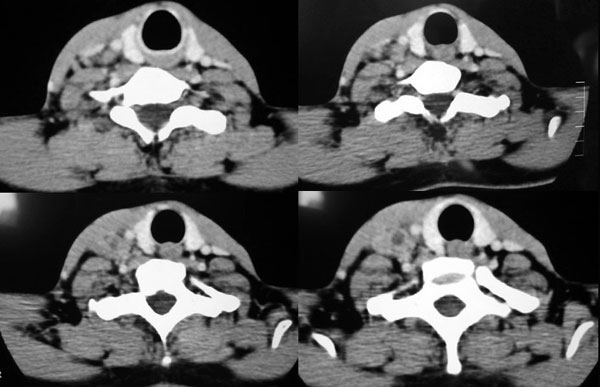

患者,谭××,男,35岁,右颈部肿痛一周,体温39度。增强待续,伪影大,对不起,请大家凑合……

右侧颈动脉间隙神经鞘膜瘤考虑。

右侧颈部软组织肿块,边界清楚,中心坏死,与周边软组织同步强化,多考虑:肿大淋巴结.不除外神经鞘膜瘤.

右颈部肌肉、血管间隙内可见不规则肿块,强化后呈多房性,间隔及壁线样强化,考虑颈部脓肿。

穿剌抽吸乳白色液体6ml,实验室检查为炎性细胞。谢谢大家精彩分析!